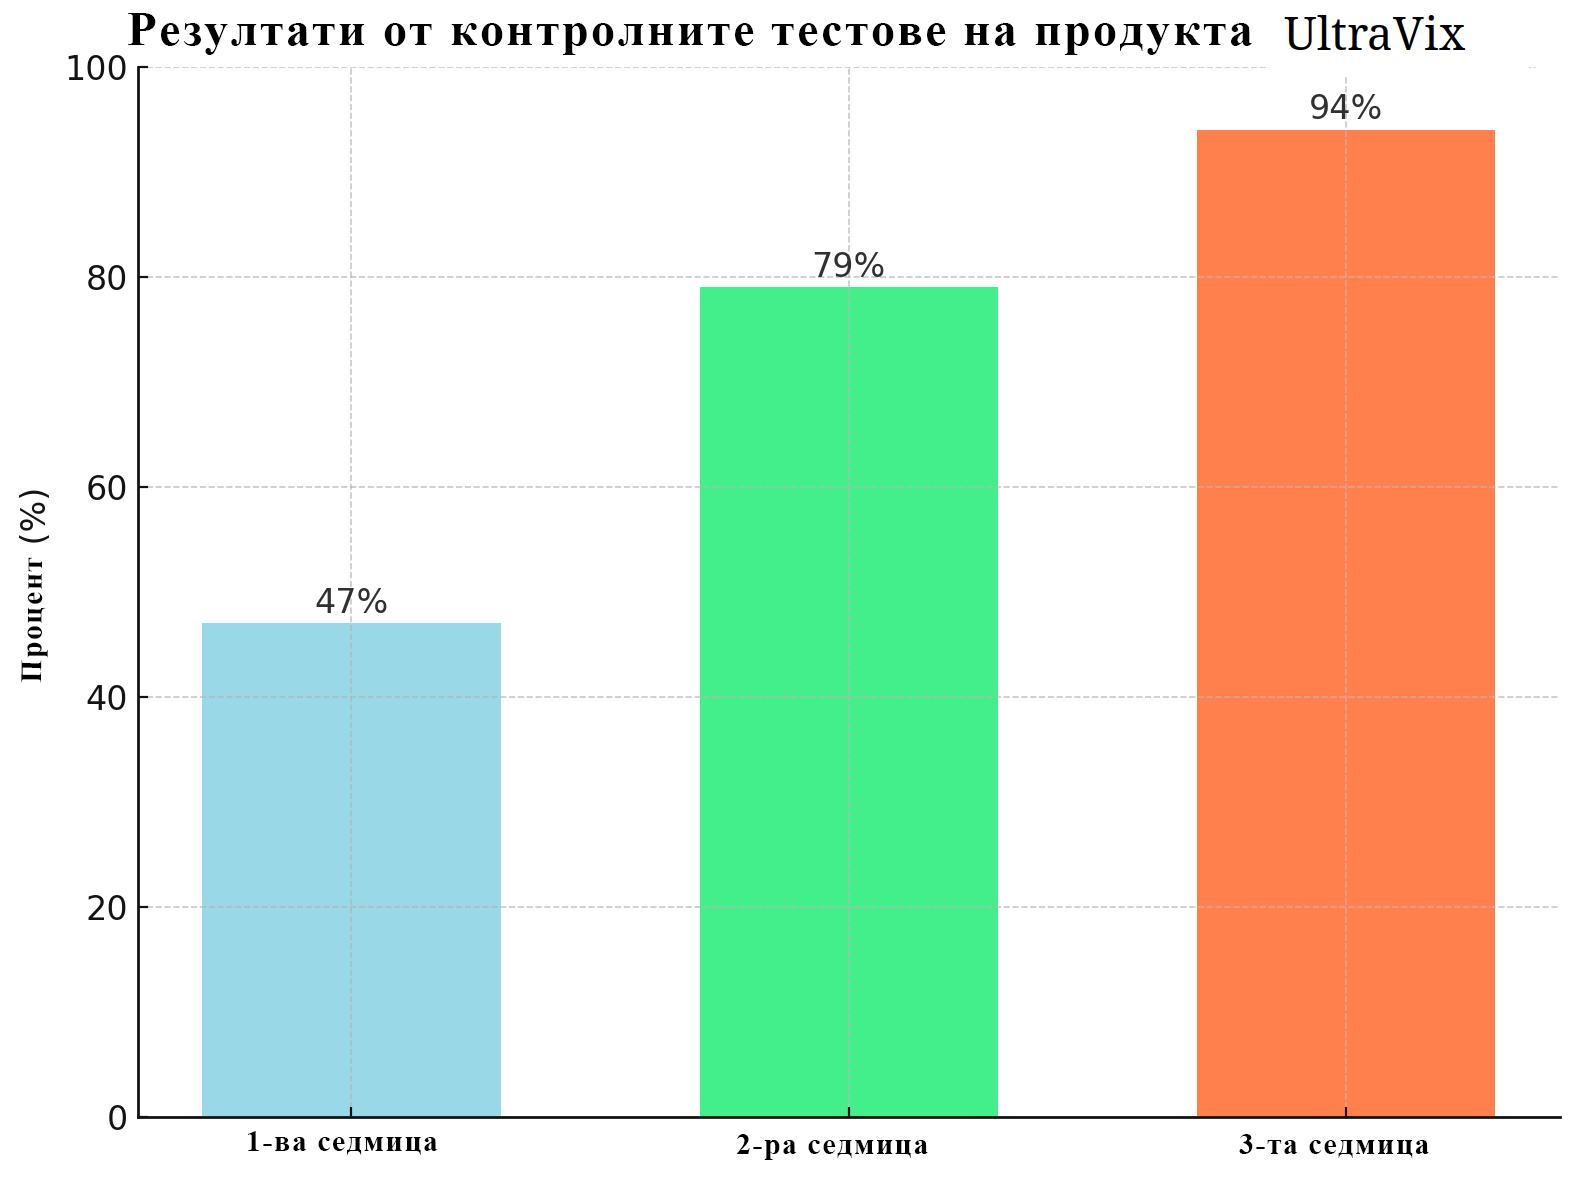

Проучване от 2023 г. беше проведено в идентични условия за две групи медикаменти, при което основният проблем на участниците беше редовен запек и нарушения в дефекацията.

Едната група използваше популярен медикамент, предписван от лекари и рекламиран по телевизията. Другата група използваше UltraVix. Резултатите впечатлиха учените. Голямото мнозинство от възстановилите се бяха от групата, която използваше UltraVix, и това изобщо не ме изненадва.